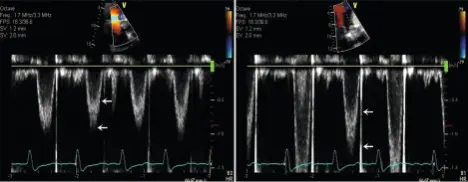

- Caption from Figure 4-6 of Oh Textbook: Examples of LVOT PWD velocity recording in a patient with atrial fibrillation. The sample volume needs to be placed about 5 mm from the aortic annulus to avoid flow acceleration. The spectral broadening (interval between two arrows with turbulent flow) should be less than 40 cm/s (left). The sample volume is too close to the aortic valve or too large in the example shown (right). Of note, there is some variation of LVOT velocity in this example because of atrial fibrillation.

- Normal values for LVOT peak velocity: 0.9 to 1.1 m/s

- Normal values for TVI: 20 to 24 cm.